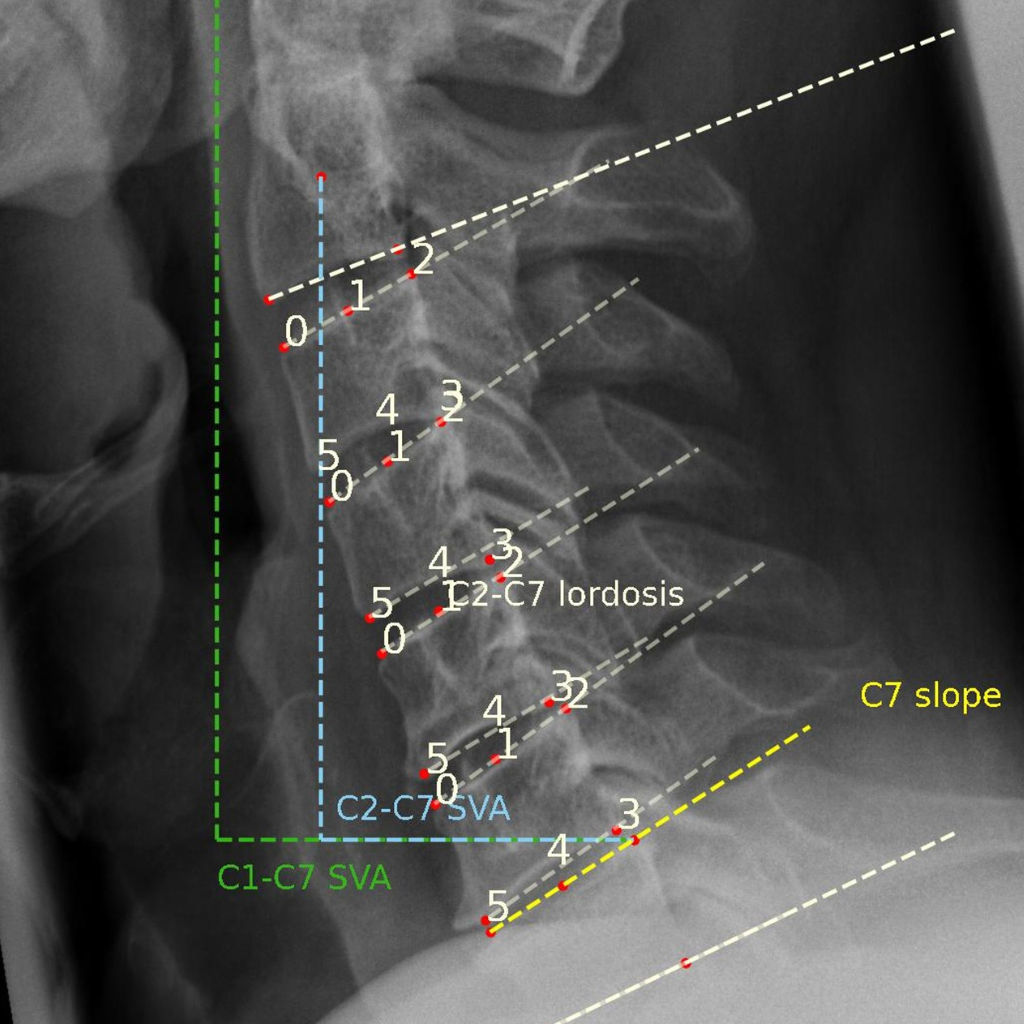

Wirbelsäule

Range of Motion (RoM)

Der maximale Bewegungsumfang, der häufig als Range of Motion (RoM) bezeichnet wird, ist ein quantitativer Parameter, der in der Bewertung der Wirbelfusion hinzugezogen wird.

RoM wird als Winkeldifferenz zweier benachbarter Wirbel in der Beuge- und Streckhaltung eines Patienten gemessen und als absoluter Wert in Grad (°) angegeben.

Die FXA-Software von RAYLYTIC misst RoM nachweislich 15-mal genauer als erfahrene Ärzte (Schulze et al., J Biomech 2011).

Typ

Quantitativ

Bildtyp

Laterale Flex/Ex

Maßeinheit

Grad (°)

Translatorische AP-Bewegung

Ein weiterer quantitativer Parameter zur Beurteilung der Wirbelsäulenfusion, die translatorische AP-Bewegung (oder Instabilität), wird als Differenz der Listhese (Wirbelgleiten) in Flexion minus der Listhese in Extension ausgedrückt.

Die Werte sind in Millimetern angegeben. Positive Werte weisen auf eine Spondylolisthese hin, negative Werte auf eine Retrolisthese.

Grad (°) oder mm